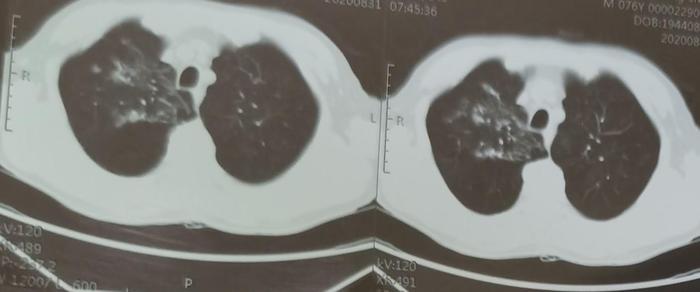

四、某些有传染性的肺结核病人。

此病人痰中检查出结核菌,确诊为肺结核,具有传染性。这是服药前的CT。

可见肺结核球状、片状发白的的影子周围有一些较淡的磨玻璃影子,这些较淡的磨玻璃影子围绕着发白的影子,也是结核的一种表现。